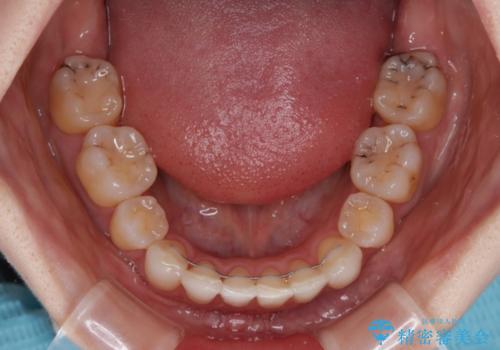

- 八重歯や前歯のデコボコを気にして来院された患者様です。

骨格的な左右差と、歯列から外れている歯が上下で左右非対称になっていることから、上下正中が歯1本分ずれている状態でした。

八重歯の改善と、上下の正中位置を極力合わせていくことを目的として、上下左右の第一小臼歯4本を抜歯し、ワイヤー装置にて矯正治療を行うこととしました。